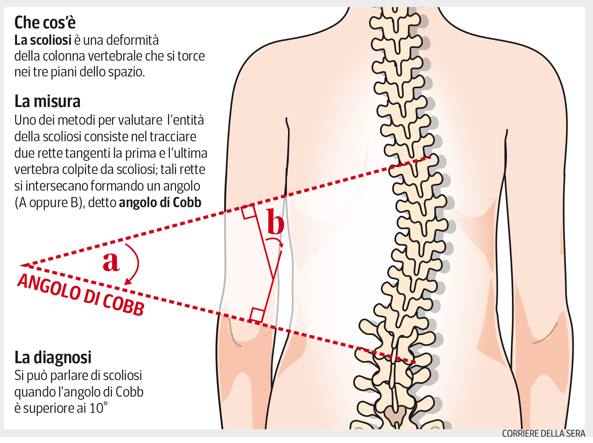

La diagnosi di una scoliosi è legata al sospetto clinico, come presenza di asimmetrie del corpo (spalle, fianchi, gibbo) ma, da definizione, per fare diagnosi di scoliosi deve essere presente una curva di 10°o superiore sul piano frontale, con rotazione vertebrale, misurati su una radiografia in piedi.

Sono sempre necessarie le radiografie?

Si quando si ha il sospetto clinico di scoliosi. Ma non bisogna mai esagerare perché fanno male Le radiografie confermano la scoliosi, permettono di misurarla e quindi vedere quanto è grave e inoltre studiando il bacino è possibile vedere a che punto è lo sviluppo scheletrico.